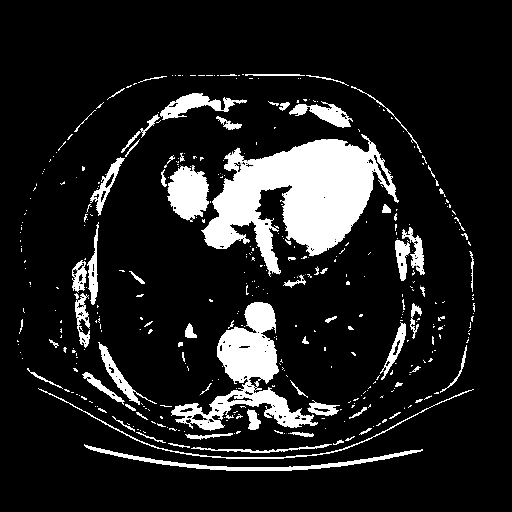

Original VENOUS CT scan

Full window (WL 1023.5, WW 4095 β†’ Low βˆ’1024, High +3071)

Actual HU range: [-1024.0, 3071.0]